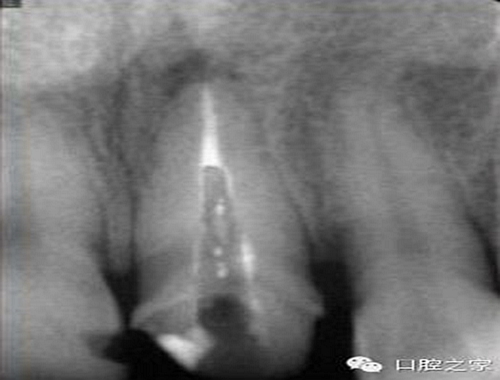

大多數(shù)醫(yī)生在樁道預(yù)備時習慣于干燥預(yù)備根管(圖 1),這樣很容易破壞根管壁的牙本質(zhì)結(jié)構(gòu),同時也可形成較厚的玷污層,影響樹脂水門汀與牙體組織的粘接。因此,臨床操作時應(yīng)選擇沖洗的方法冷卻預(yù)備根管(圖 2),防止牙膠及封閉劑粘連附著于根管壁形成第二玷污層(根管治療時形成的玷污層稱為第一玷污層),有利于樹脂水門汀與根管牙本質(zhì)的粘接。

圖1:干燥預(yù)備根管。

圖2:沖洗預(yù)備根管。